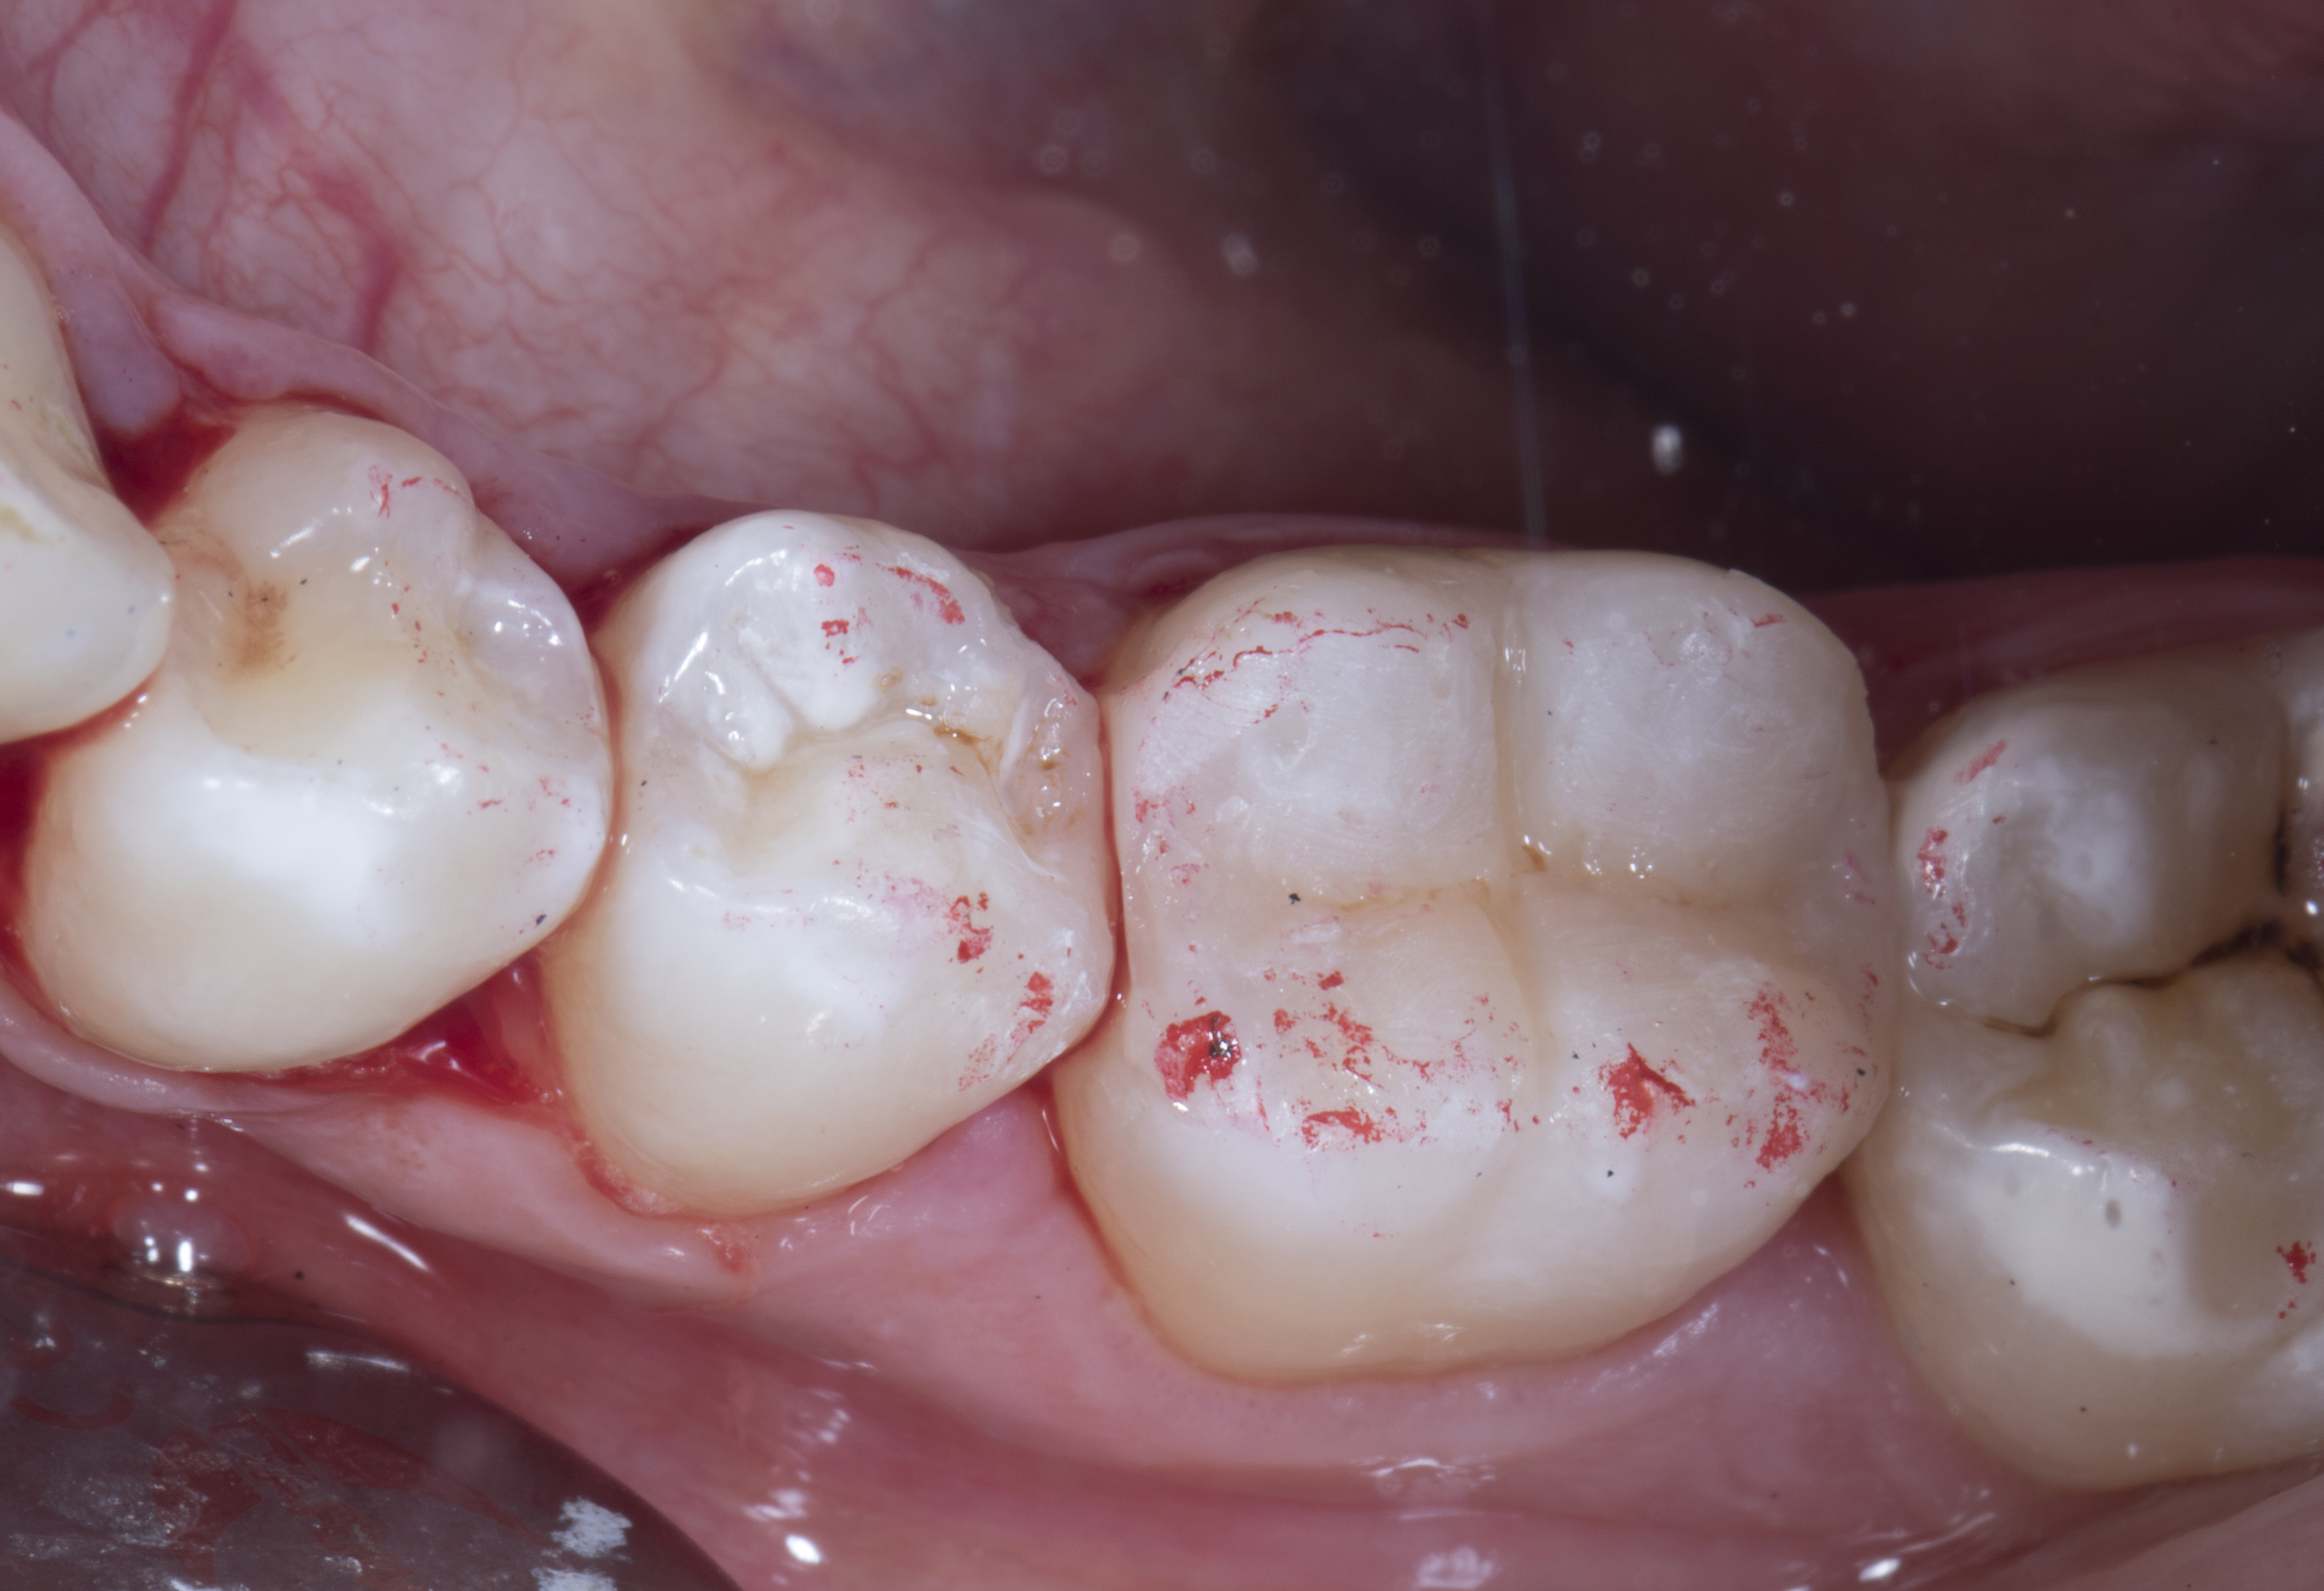

Step 11 – The rubber dam was removed and occlusion checked with 40 micron articulating paper in static occlusion and again in dynamic occlusion with patient in upright position.

Figure 11

Figure 11. Rubber dam was removed and occlusion checked with 40 micron articulating paper in static occlusion.